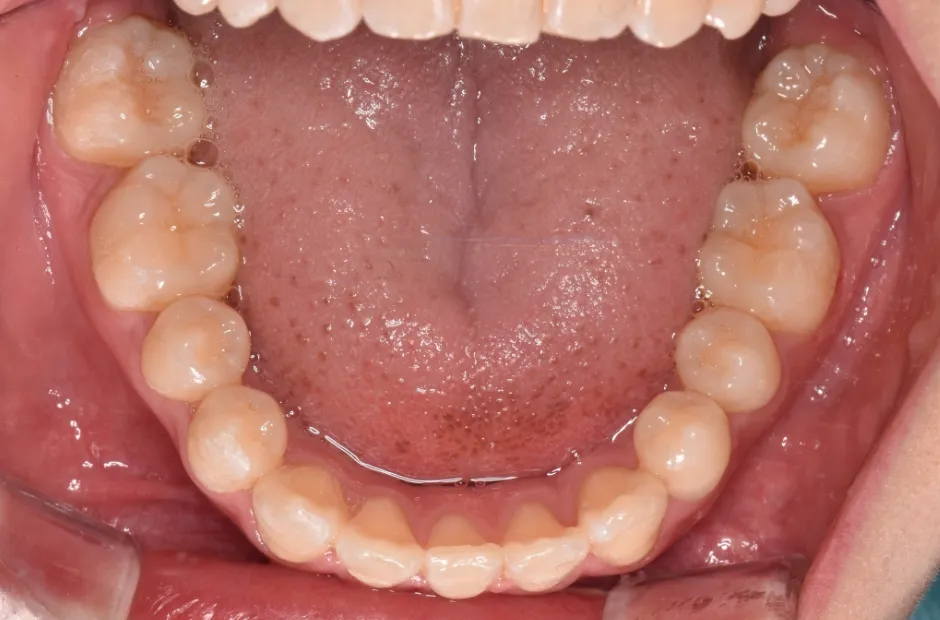

反対咬合

| 診断名・主訴 | 前歯反対咬合 |

|---|---|

| 年齢・性別 | 12歳・男性 |

| 治療期間・回数 | 1年半 18回 |

| 治療に用いた主な装置 | リンガルアーチ(前方誘導弾線) |

| 抜歯部位 | なし |

| 治療費 | 35万円(税抜) |

| リスク・副作用 | 装置による違和感・疼痛・歯肉退縮・歯根吸収・虫歯のリスクなど |

治療前

治療中

治療後